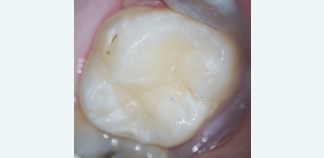

До лечения

Жалоб нет. Пациент пришел на осмотр.

Пациенту 27 лет.

Как лечили

Пролечен множественный кариес зубов.

Лечение проведено за четыре визита.